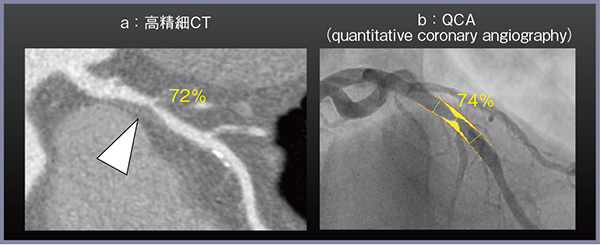

キヤノンメディカルシステムズの高精細CT「Aquilion Precision」は,0.25mm×160列の検出器を搭載し,従来CTの検出器(0.5mm)の半分のスライス幅を実現している。これにより,病変を詳細に評価可能となり,高精細CTを用いて定量的冠動脈造影法(quantitative coronary angiography:QCA)と同等の定量性にて冠動脈狭窄病変の評価が可能となった(図1)。冠動脈CTは,初期には陰性適中率の高い検査として認識されていたが,高精細CTでは陽性適中率が向上し1),病変が有意狭窄であるかどうかを定量的に評価可能な検査として進歩を遂げた。

図1 冠動脈狭窄の定量評価